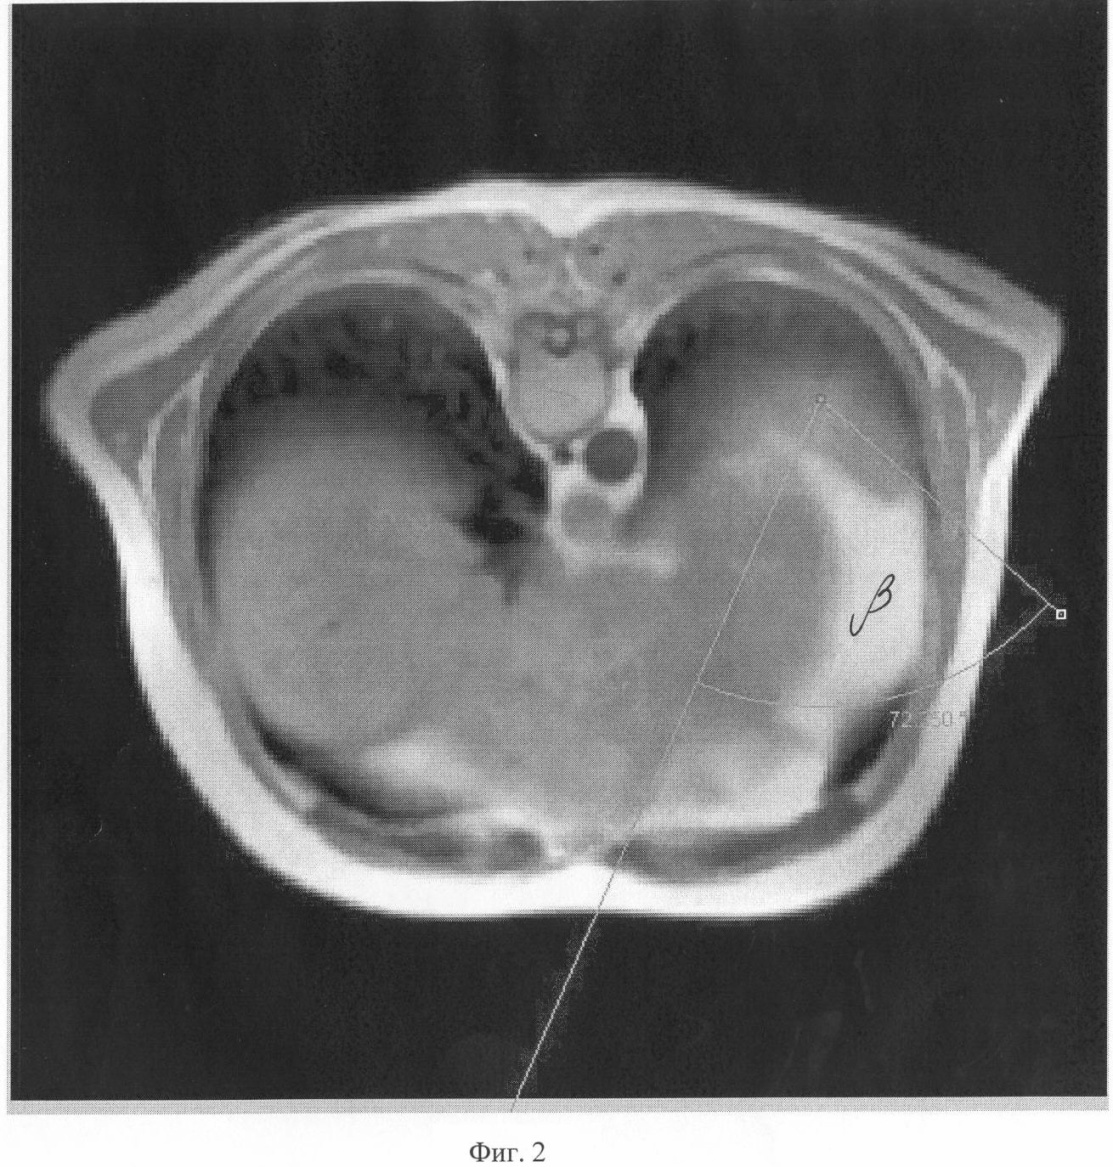

На Фиг.2 показан угол на аксиальной проекции, с ориентацией на сосудистый пучок селезенки.

Измерялись углы между оптической осью эндоскопа (ось операционного действия) и манипуляционными портами и УОД – углы , , , при этом вершина угла ориентировалась на сосудистую ножку селезенки примерно в 2 см от ее ворот (Фиг.1-3) и на оба полюса селезенки (Фиг.6). Углам приданы следующие обозначения:

В прямой проекции (Фиг.1) выбирают направление в свободном пространстве между органами брюшной полости с прицелом на сосудистый пучок селезенки, точку А, в пределах 25-90° между осями инструментов, программа запоминает эту позицию. Выбирают положение векторов в аксиальной проекции (Фиг.2), затем в сагиттальной Фиг.3. Строят итоговое объемное трехмерное изображение совмещением трех срезов и векторов с проекцией на кожу (Фиг.4, 5). При этом величину углов можно задавать автоматически, векторы перемещаются в новое положение и находят новые рабочие точки Г, Д, Е (Фиг.5) для введения инструментов. Проверяют длину новых векторов, проверяя, не превышает ли их длина рабочую длину инструментов. Если три условия выполнения лапароскопической операции не получены, то вновь производят подбор новых точек, изменяя величину углов. Проводят контрольное позиционирование на крайние точки зоны операции на органе-мишени Б и В (Фиг.6). Строят биссектрису угла . Проверяют длину векторов от точек Б и В на поверхности органа до вновь найденных точек на поверхности тела Г, Д, Е, она не должна превышать рабочую длину инструментов. Проверяют величину углов. Если условия не выполняются, то вновь изменяют величины углов , , и находят оптимальный вариант. После того как новые точки для введения инструментов найдены на визуализированной поверхности, переносят их на кожу пациента, ставя новые метки другим маркером, например зеленкой в точках Г, Д, Е. Троакары в ходе операции вводят во вновь определенные точки.